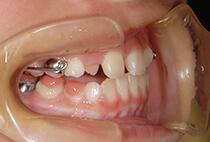

5歳6ヶ月、受け口が気になるとお母様と一緒にご来院。

「幼稚園の間に治療スタートしたい」「小学校入学時には装置に慣れた状態でいたい」とのご希望で、矯正治療をスタートしました。

治療は、急速拡大+前方けん引装置から。

3ヶ月で骨格バランスが大きく改善し、1年3ヶ月後にはさらにバランスの整ったお顔立ちへ。

成長に合わせて3回の急速拡大を行い、夜間のマウスピースとお口の機能訓練で成長をサポート。小学生を正常なバランスで過ごすことができました。

中学校入学と同時にマウスピースを卒業し、今後は予防管理へ移行予定です。

「早めに始めてよかった」と喜んでいらっしゃいます。

5歳6ヶ月、受け口が気になり、お母様と一緒にご来院。

治療は、急速拡大+前方牽引装置から。

1ヶ月で骨格バランスが大きく改善しました。

小学1年生の7ヶ月後には、さらにバランスの整った噛み合わせに。

成長に合わせて3回の急速拡大を行い、夜間のマウスピースとお口の機能訓練で成長をサポート。

小学生を正常なバランスで過ごすことができました。